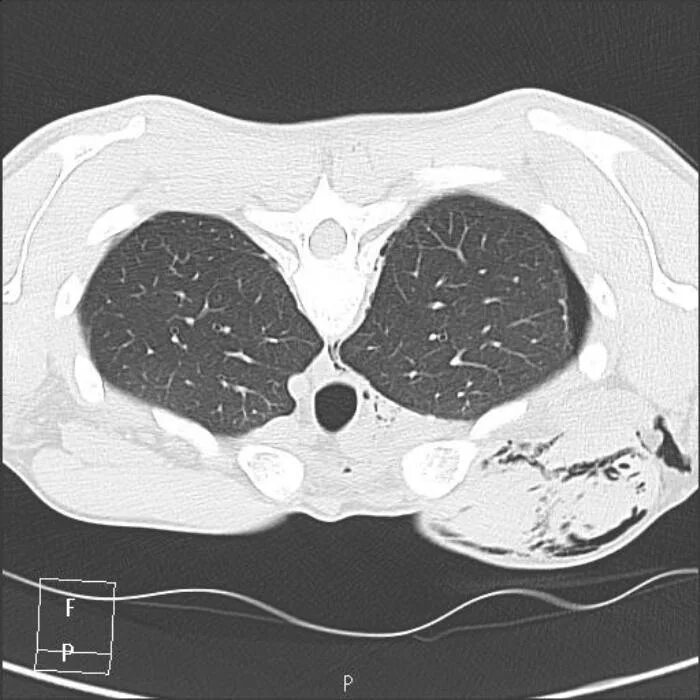

Подготовка к кт грудной и брюшной полости